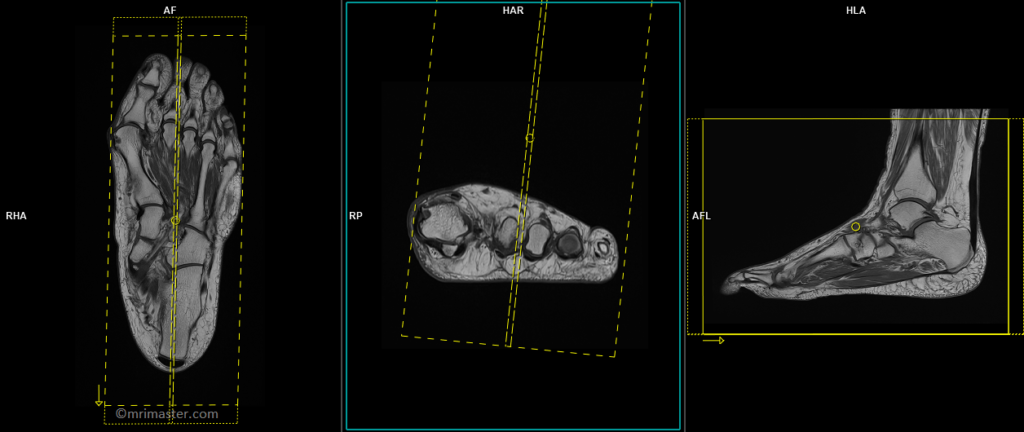

T1 tse coronal 3mm

Plan the coronal slices on the sagittal plane, angling the position block parallel to the metatarsal and phalanges bones. Check the positioning block in the other two planes. An appropriate angle must be given in the axial plane, parallel to the line across the metatarsal bones. Slices must be sufficient to cover the foot from the plantar aspect up to the dorsal aspect. Most of the radiologists refer this as a coronal plane even though in anatomical position this is an axial plane.

T2 stir coronal 3mm

T1 tse sagittal 3mm

Plan the sagittal slices on the coronal plane and angle the positioning block parallel to the metatarsal and phalanges bones. Check the positioning of the block in the other two planes. An appropriate angle must be established in the axial plane, perpendicular to the metatarsal bones. Ensure that the slices are sufficient to cover the foot from side to side.

T2 stir sagittal 3mm